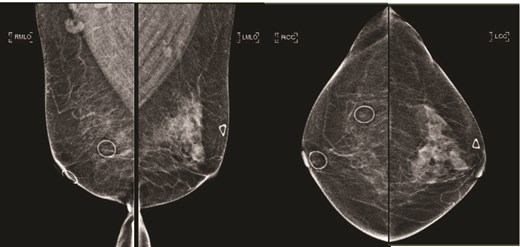

(Left) Ultrasound image of the left breast hypoechoic lesion; (Right) Ultrasound image of one of several enlarged lymph nodes with effacement of fatty hilum.

(Left) Mammography cranial-caudal view of left breast; (Right) Mammography mediolateral oblique view of the left breast: Left upper outer breast spiculated mass with minimal architectural distortion.